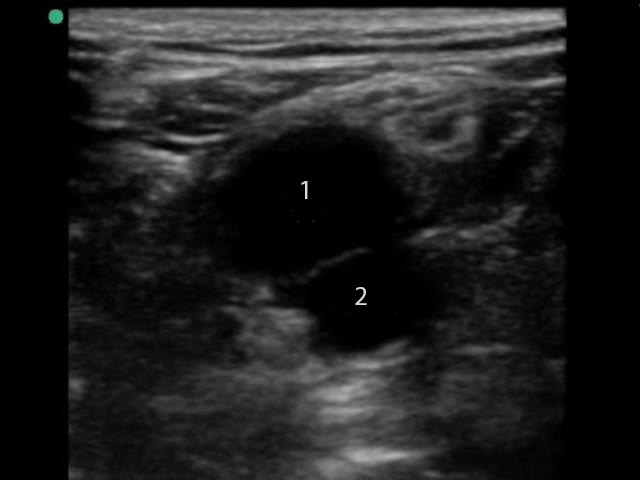

Deep Vein Thrombosis (DVT) Popliteal Vessels Image

Popliteal Vein

Popliteal Artery